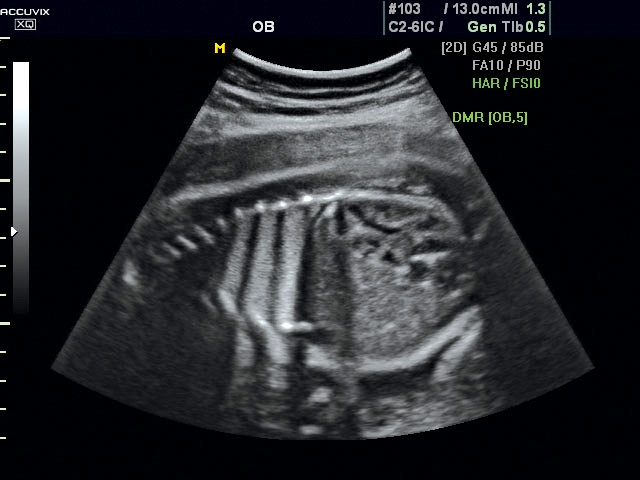

A pontos analízis és diagnózis iránti egyre növekvő igény kiszolgálására a MEDISON egy új real time képfeldolgozó technológiát fejlesztett ki Dynamic MR™ elnevezéssel. Az eljárás a diagnosztikus ismeretanyagot a precizitás és a pontosság egy teljesen új szintjére emeli. Használata az alapvető 2D ultrahang képinformáció real time, kivételesen kristálytiszta és kiemelkedően részletezett megjelenítését teszi lehetővé tűéles kontúrok és finoman rajzolt szövetstruktúra mellett. A DMR™  technológia ideális eszköze az ultrahang-diagnosztikának kezdve a szülészet-nőgyógyászattól a foetalis echon át az általános alkalmazásokig.

Magzati koponya képe normál 2D módbanMagzati koponya 2D képe bekapcsolt Dynamic MR funkcióvalMagzat törzsének képe normál 2D módbanMagzat törzsének képe bekapcsolt Dynamic MR funkcióvalMagzat felsőajakjának és orrának képeMagzat felsőajakjának és orrának képe bekapcsolt Dynamic MR funkcióval

A DynamicMR alkalmazása az átlagos ultrahang teljesítményt a zaj és szemcsézettség jellegű műtermékek kiszűrése révén a vizuális diagnosztika, a precizitás és a pontosság új szférájába emeli. Figyelje meg a cerebellum, CSP és cisterna magna élstruktúráit, mennyire pontosan definiáltak és a teljes agyi struktúra ábrázolása a Dynamic MR alkalmazásával milyen látványosan javul.